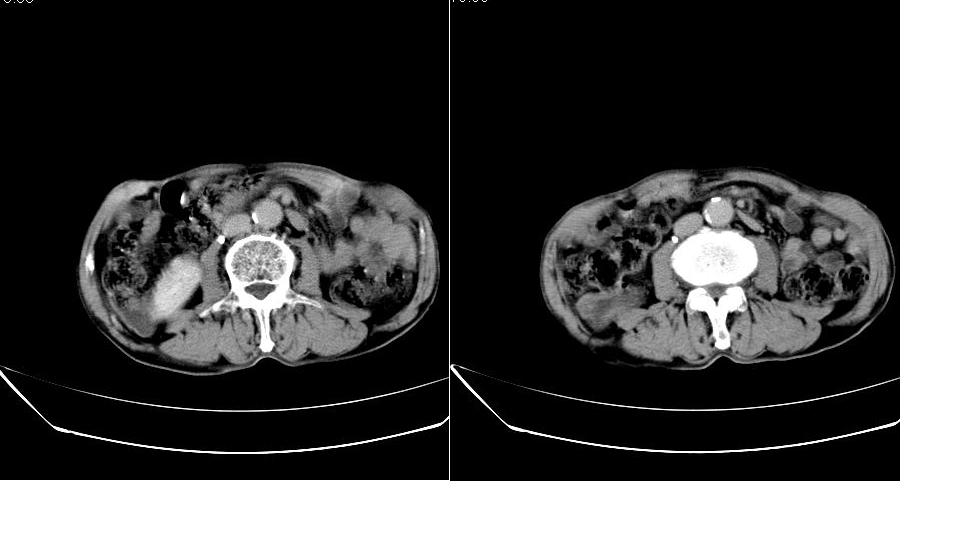

男,76岁,上腹部疼二天来就诊,彩超提示肝左叶占位,随后做上腹部ct平扫,今天做上腹部ct增强扫描,手工推药,效果不好,请谅解。

肝左叶s4肿块强化形式大概是:慢进慢出,逐渐强化----考虑血管瘤/腺瘤?{动脉期应更提前扫}。

1)肝右叶前段低密度灶,不排除肝癌可能;建议查afp。2)右肾上极囊肿。

肝内胆管积气扩张,胆囊增大,肝右前叶低密度灶,逐渐强化,一元论,胆系感染,局限性肝脓肿;右肾囊肿。

考虑肝s4段肝脓肿可能?未排除肝癌。右肾上极囊肿。